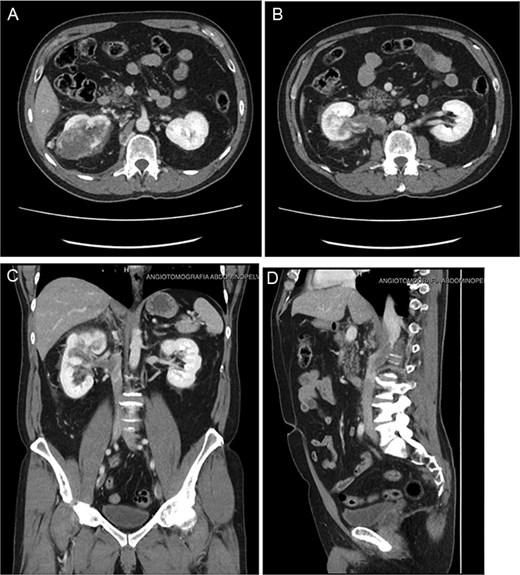

Follow-up CT imaging (Fig. 3A–D) showed a reduction in both the tumor and thrombus size, leading to the classification of the thrombus from Stage IV to Stage III according to the Mayo Clinic classification.

(A–D) Abdominopelvic contrast-enhanced computed tomography post-neoadjuvant therapy showed a significant reduction in tumor size and the involvement of the thrombus in the azygos vein.

Based on these post-treatment findings, a joint decision with Urology was made to avoid a thoraco-phreno-laparotomy, opting instead for an extended supra-infraumbilical right subcostal laparotomy.